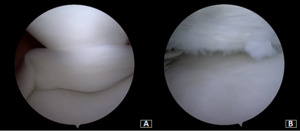

Under general anesthesia, a left knee arthroscopy using standard anterolateral and anteromedial portals. An incomplete type medial discoid meniscus with an atypical hypertrophic posterior root and an enlargement of the body and the posterior horn of the meniscus was found (Figure 3A). In addition, instability of the posterior horn, with a lack of rear tibial attachments, was observed (Figure 3B). Saucerization of the central discoid element was performed until an average meniscal width and semilunar shape was reached (Figure 4A). Two outside-in sutures with absorbable stitches were thus applied to repair the horizontal tear and stabilize the meniscus’s peripheral rim to the knee capsule (Figure 4B). A probe was used to assess the repair’s tightness and stability. Because the right knee was paucisymptomatic, no treatment was performed.